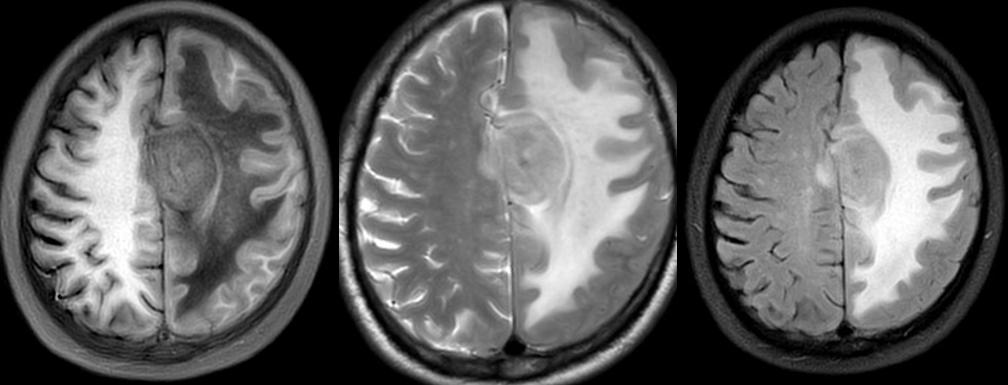

CT:左侧额叶大脑镰旁见一大小约2.2X28m类圆形略高密度团块,CT值43.7Hu,边界尚清,以宽基底接于大脑镰,周围额顶部脑白质内见大片低密度水肿区。双侧基底节区、放射冠区、侧脑室周围白质及皮层下区见多发斑点状、斑片状低密度灶。左侧侧脑室较对侧宽。部分脑沟、脑裂、池增宽。中线结构尚居中。

MRI:左侧颅底区可见金属伪影干扰。左侧额部大脑镰旁见一类圆形等长 T1 等长 T2异常信号T2 Flair 呈近等信号,中心见点状长T1短T2信号灶,病灶大小约3.3X3.7X3.cm,DWI(b=1000)及ADC 图示病灶轻度扩散受限,增强扫描呈明显不均匀强化,邻近部分硬脑膜可见线状强化,病灶周围脑实质见大片状长 T1 长 T2水肿信号,周围脑实质及双侧侧脑室受压变窄,左侧大脑半球脑沟裂变浅,中线结构右移。脑桥、双侧基底节区、双侧侧脑室旁白质、右侧放射冠及皮层下见多发斑点状、斑片状等长T1长T2异常信号灶,T2Flair 高信号,DMI未见明显扩散受限。右侧上颌窦粘膜增厚。